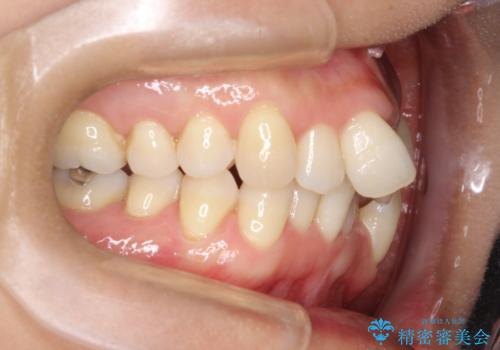

重度のガタガタのインビザラインによる非抜歯矯正

- 上下の歯のガタガタを主訴に来院されました。

インビザラインで奥歯を後方に移動させるのと、歯と歯の間をわずかに削ることでスペースを作り、歯を並べる計画としました。

しっかりとマウスピースを使用していただけたので、順調に治療を終えることができました。